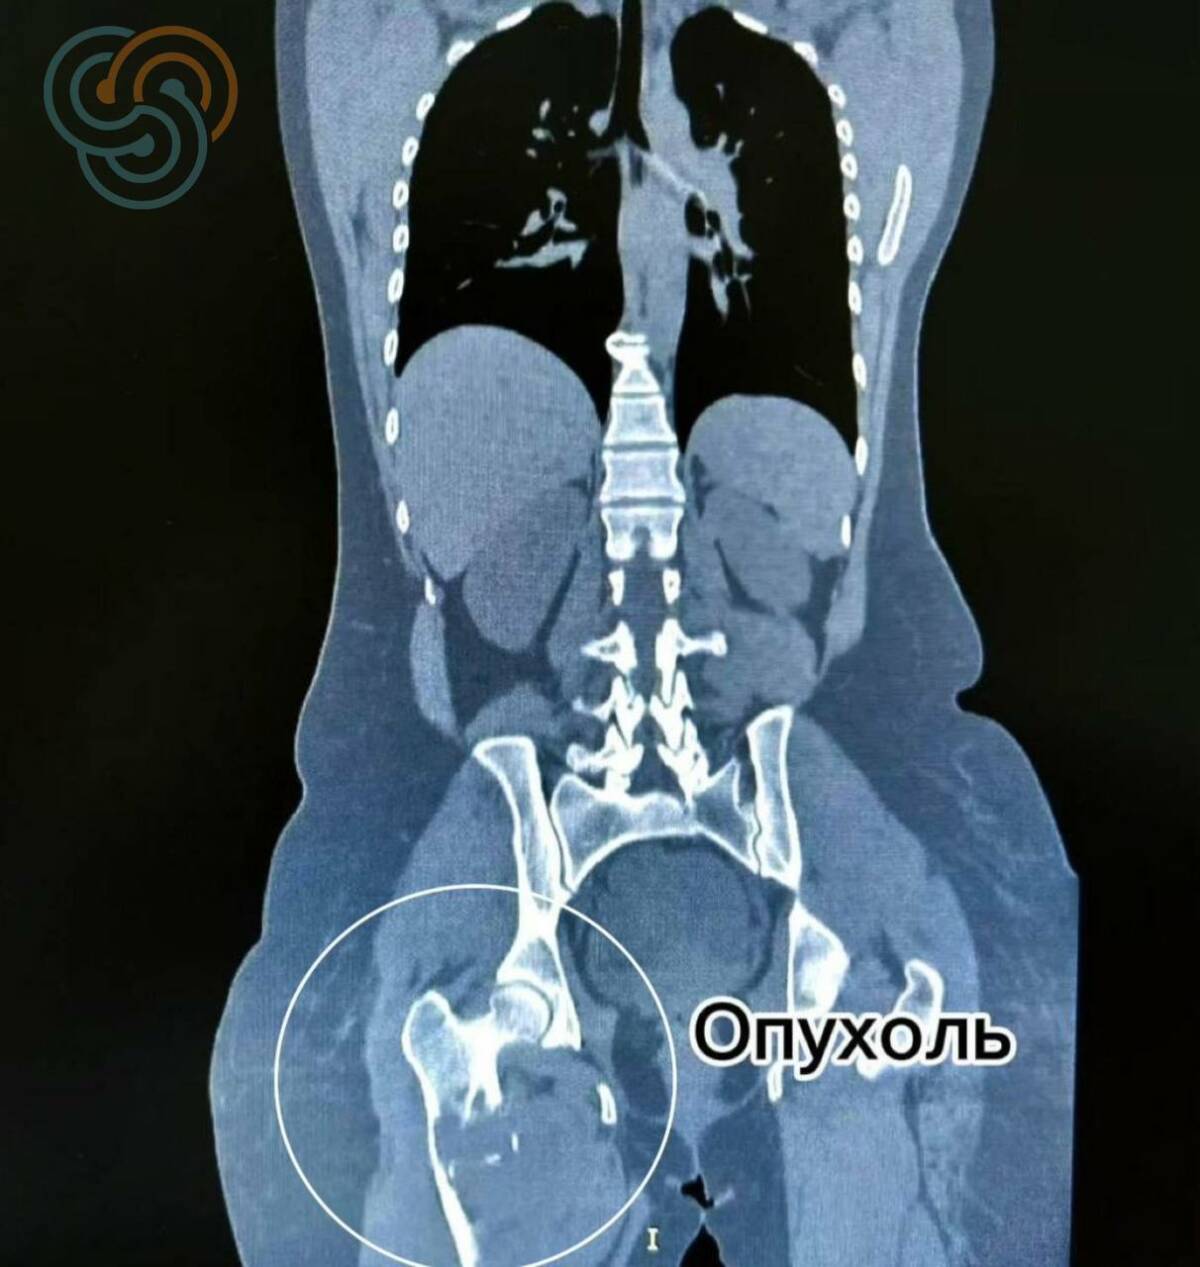

В Татарстане врачи Республиканского клинического онкологического диспансера заменили пациентке бедренную кость, пораженную саркомой. Об этом сообщила пресс-служба медицинского учреждения.

В апреле женщина столкнулась с болью в ноге, которая продолжительное время не утихала. На обследовании был поставлен диагноз «саркома». Во время ожидания результатов анализа биопсии в федеральном центре опухоль разрушала бедренную кость и вскоре произошло одно из самых тяжелых осложнений – патологический перелом. В большинстве подобных случаев пациентам ампутируют ногу.

«Объем поражения был крайне большим – фактически затронута вся бедренная кость. Здесь нам удалось выполнить радикальное хирургическое вмешательство с сохранением конечности», – отметил заведующий онкологическим отделением № 16 Ильдар Сафин.